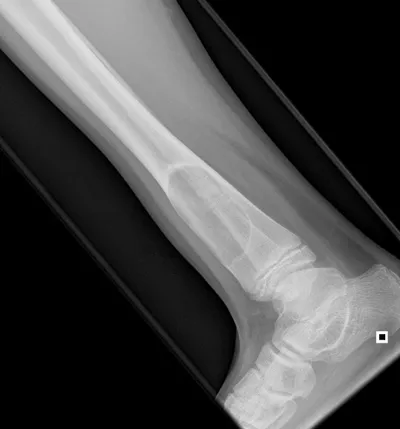

Browse 8 medical images tagged with benign. This collection includes various imaging modalities for medical education and reference.

- This collection contains 8 radiology images related to benign, including various imaging modalities such as X-rays, MRIs, CT scans, and ultrasound images commonly used in medical diagnosis and education.